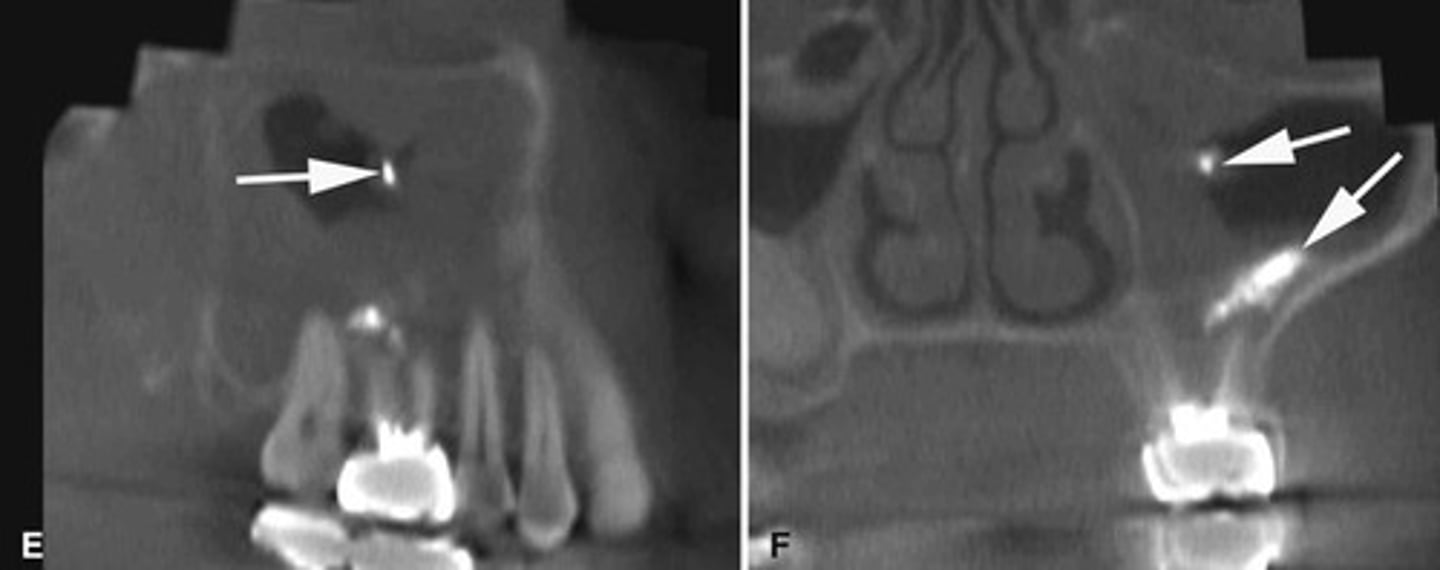

Completed around 20years; discontinuity of cortication for adults would indicate pathology (arthritic changes) , but in kids thin or no cortical border would be normal.

When is complete calcification of the cortical boarders of the condyle completed? What would be indicated by lack of cortication after that time?

The bottom radiographs depict a developing 7year-old child.

1. The cortication of all the articulating surfaces are thin.

2. The mandibular fossa is shallow

3. The articular eminence is short

The top images are being compared to the bottom images, which patient is younger and what are all the ways to know this.